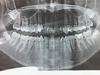

В общем, установка вместе с прелюдиями, самим процессом и разговором по душам после - около сорока минут. Я даже и не заметила, для меня они как пятнадцать пролетели. Потом всё время казалось, что у меня немного приоткрыт рот - брекеты в нем не помещаются - но это иллюзия, конечно же

Ничего пока не болит(за одним исключением), приятное ощущение стянутости - мне нравится. Только вот очень болит пятерка при надкусывании, и только она одна - это нормально, жить буду?